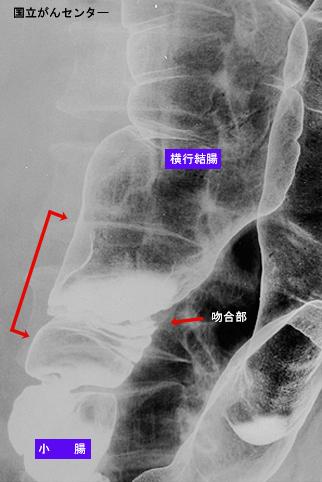

症例提示(所在地,施設名等): 東京都・ 国立がんセンター中央病院と九州がんセンターの共同作成

症例登録日 2003/09/01

画像ID:5635

疾患(病理主体)の分類悪性上皮性腫瘍/腺癌

部位(臓器別)2つ以上の臓器/

検査方法X-P

病変の最大径(ミリ)40以上